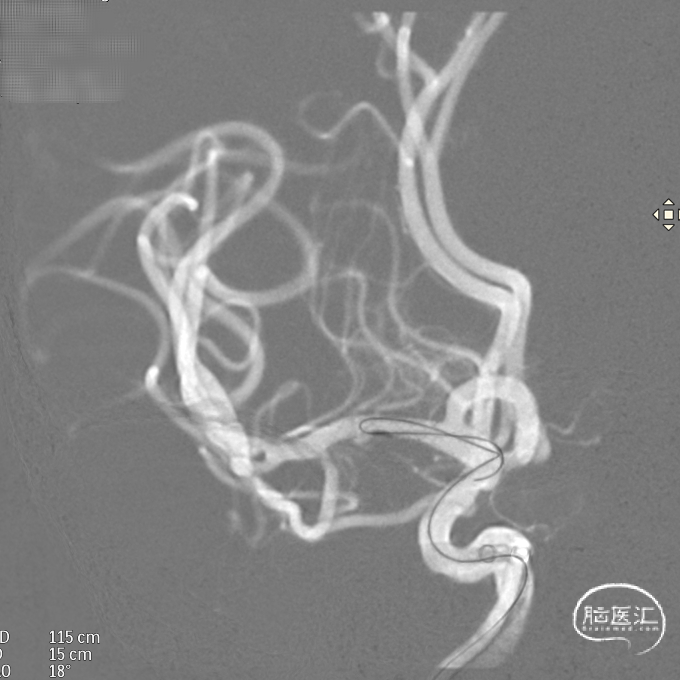

支架到位,远端打开(正侧位):4.75-20mm支架在大脑中动脉M1段打开,回撤至C6段远端锚定。支架释放过程中,轻柔推送支架系统,可见支架导管沿血管壁大弯侧走行,支架打开良好。

支架中段打开:

输送导丝及微导管回撤:释放至支架末端,减张系统,回撤支架导管,释放支架。沿支架推送杆,调节系统张力,将支架导管通过支架到达C7段。

支架内使用成襻微导丝进行按摩,使支架充分贴壁。

术后造影:支架覆盖两枚动脉瘤瘤颈,贴壁良好,瘤体内可见造影剂滞留。

术后支架显影: